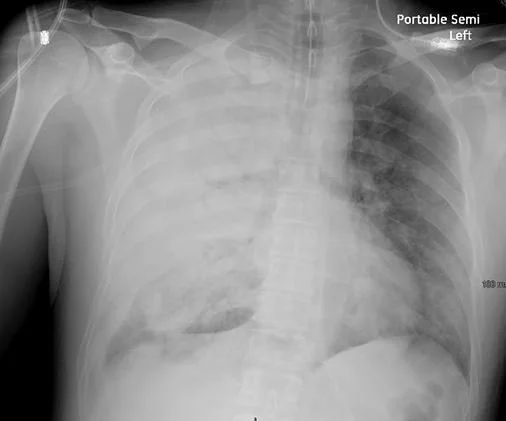

Anthrax- Bacillus cereus, traditionally thought to be a foodborne pathogen, has been associated with an anthrax-like disease in humans.  Currently the most cases have been found in Louisiana and Texas in welders.  In cases studied, B. cereus had acquired the anthrax plasmid pX01 and pXO2  which enable it to cause a severe and often fatal disease. The abnormal CXR and fever may be the presenting signs. This IS NOT Bacillus anthracis although both inhaled anthrax and B. cereus can present with abnl CXRs.

39 y.o. with welder’s anthrax from B cereus who received .the anthrax monoclonal antitoxin, raxibacumab.